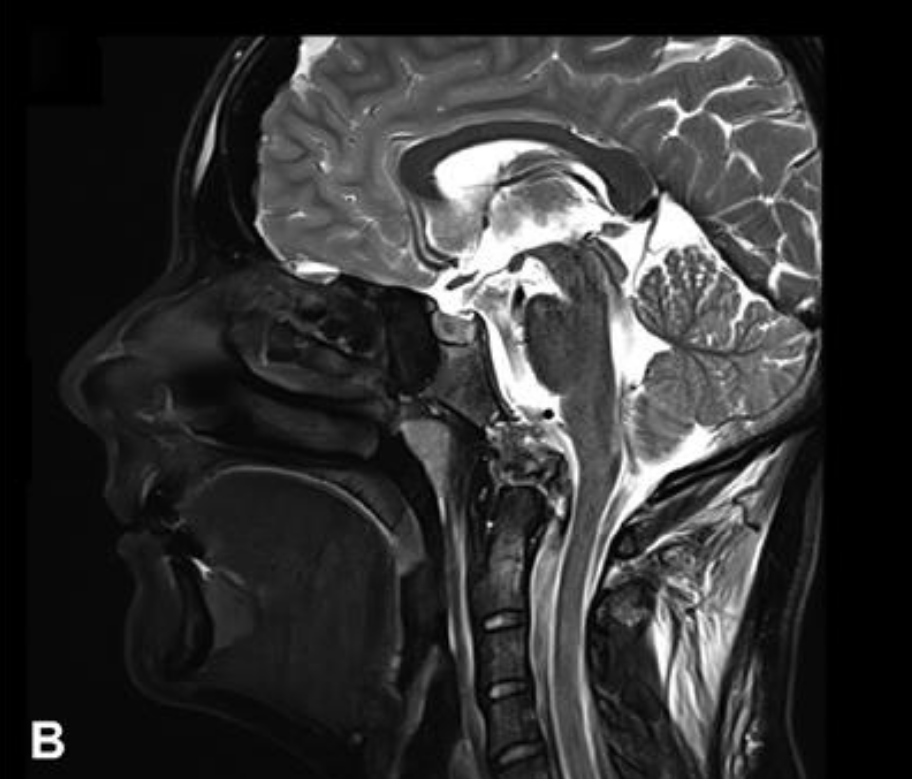

这位年轻女性因颈部疼痛就诊,MRI发现颅颈交界区脊索瘤,伴骨质破坏和硬膜内延伸,累及双侧椎动脉。

术前MRI

手术策略:INC福洛里希教授采用了内镜辅助的前外侧入路,顺利切除肿瘤。术后几天行枕颈融合术确保稳定性。

术后MRI